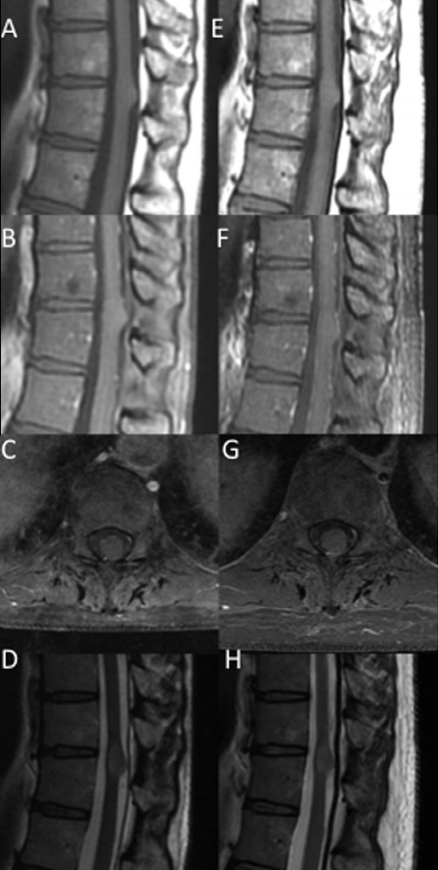

病人说明:一位44岁的妇女因腰痛接受了下背部MRI检查。(A)矢状面t1加权MRI显示T8 T9处有外生性/膨胀性病变。(B) MRI t1加权造影剂显示病变在给予造影剂后没有增强。(C)病灶t1加权轴位造影,显示病灶浸润性质。(D) T2加权矢状面图像。(E)两年后,t1加权矢状位图像显示病变大小保持不变。(F)对比剂在t1加权成像上仍然没有增强。(G)轴向t1加权MRI造影剂。(H) t2加权矢状面图像。由于患者持续无症状表现,未进行活检。